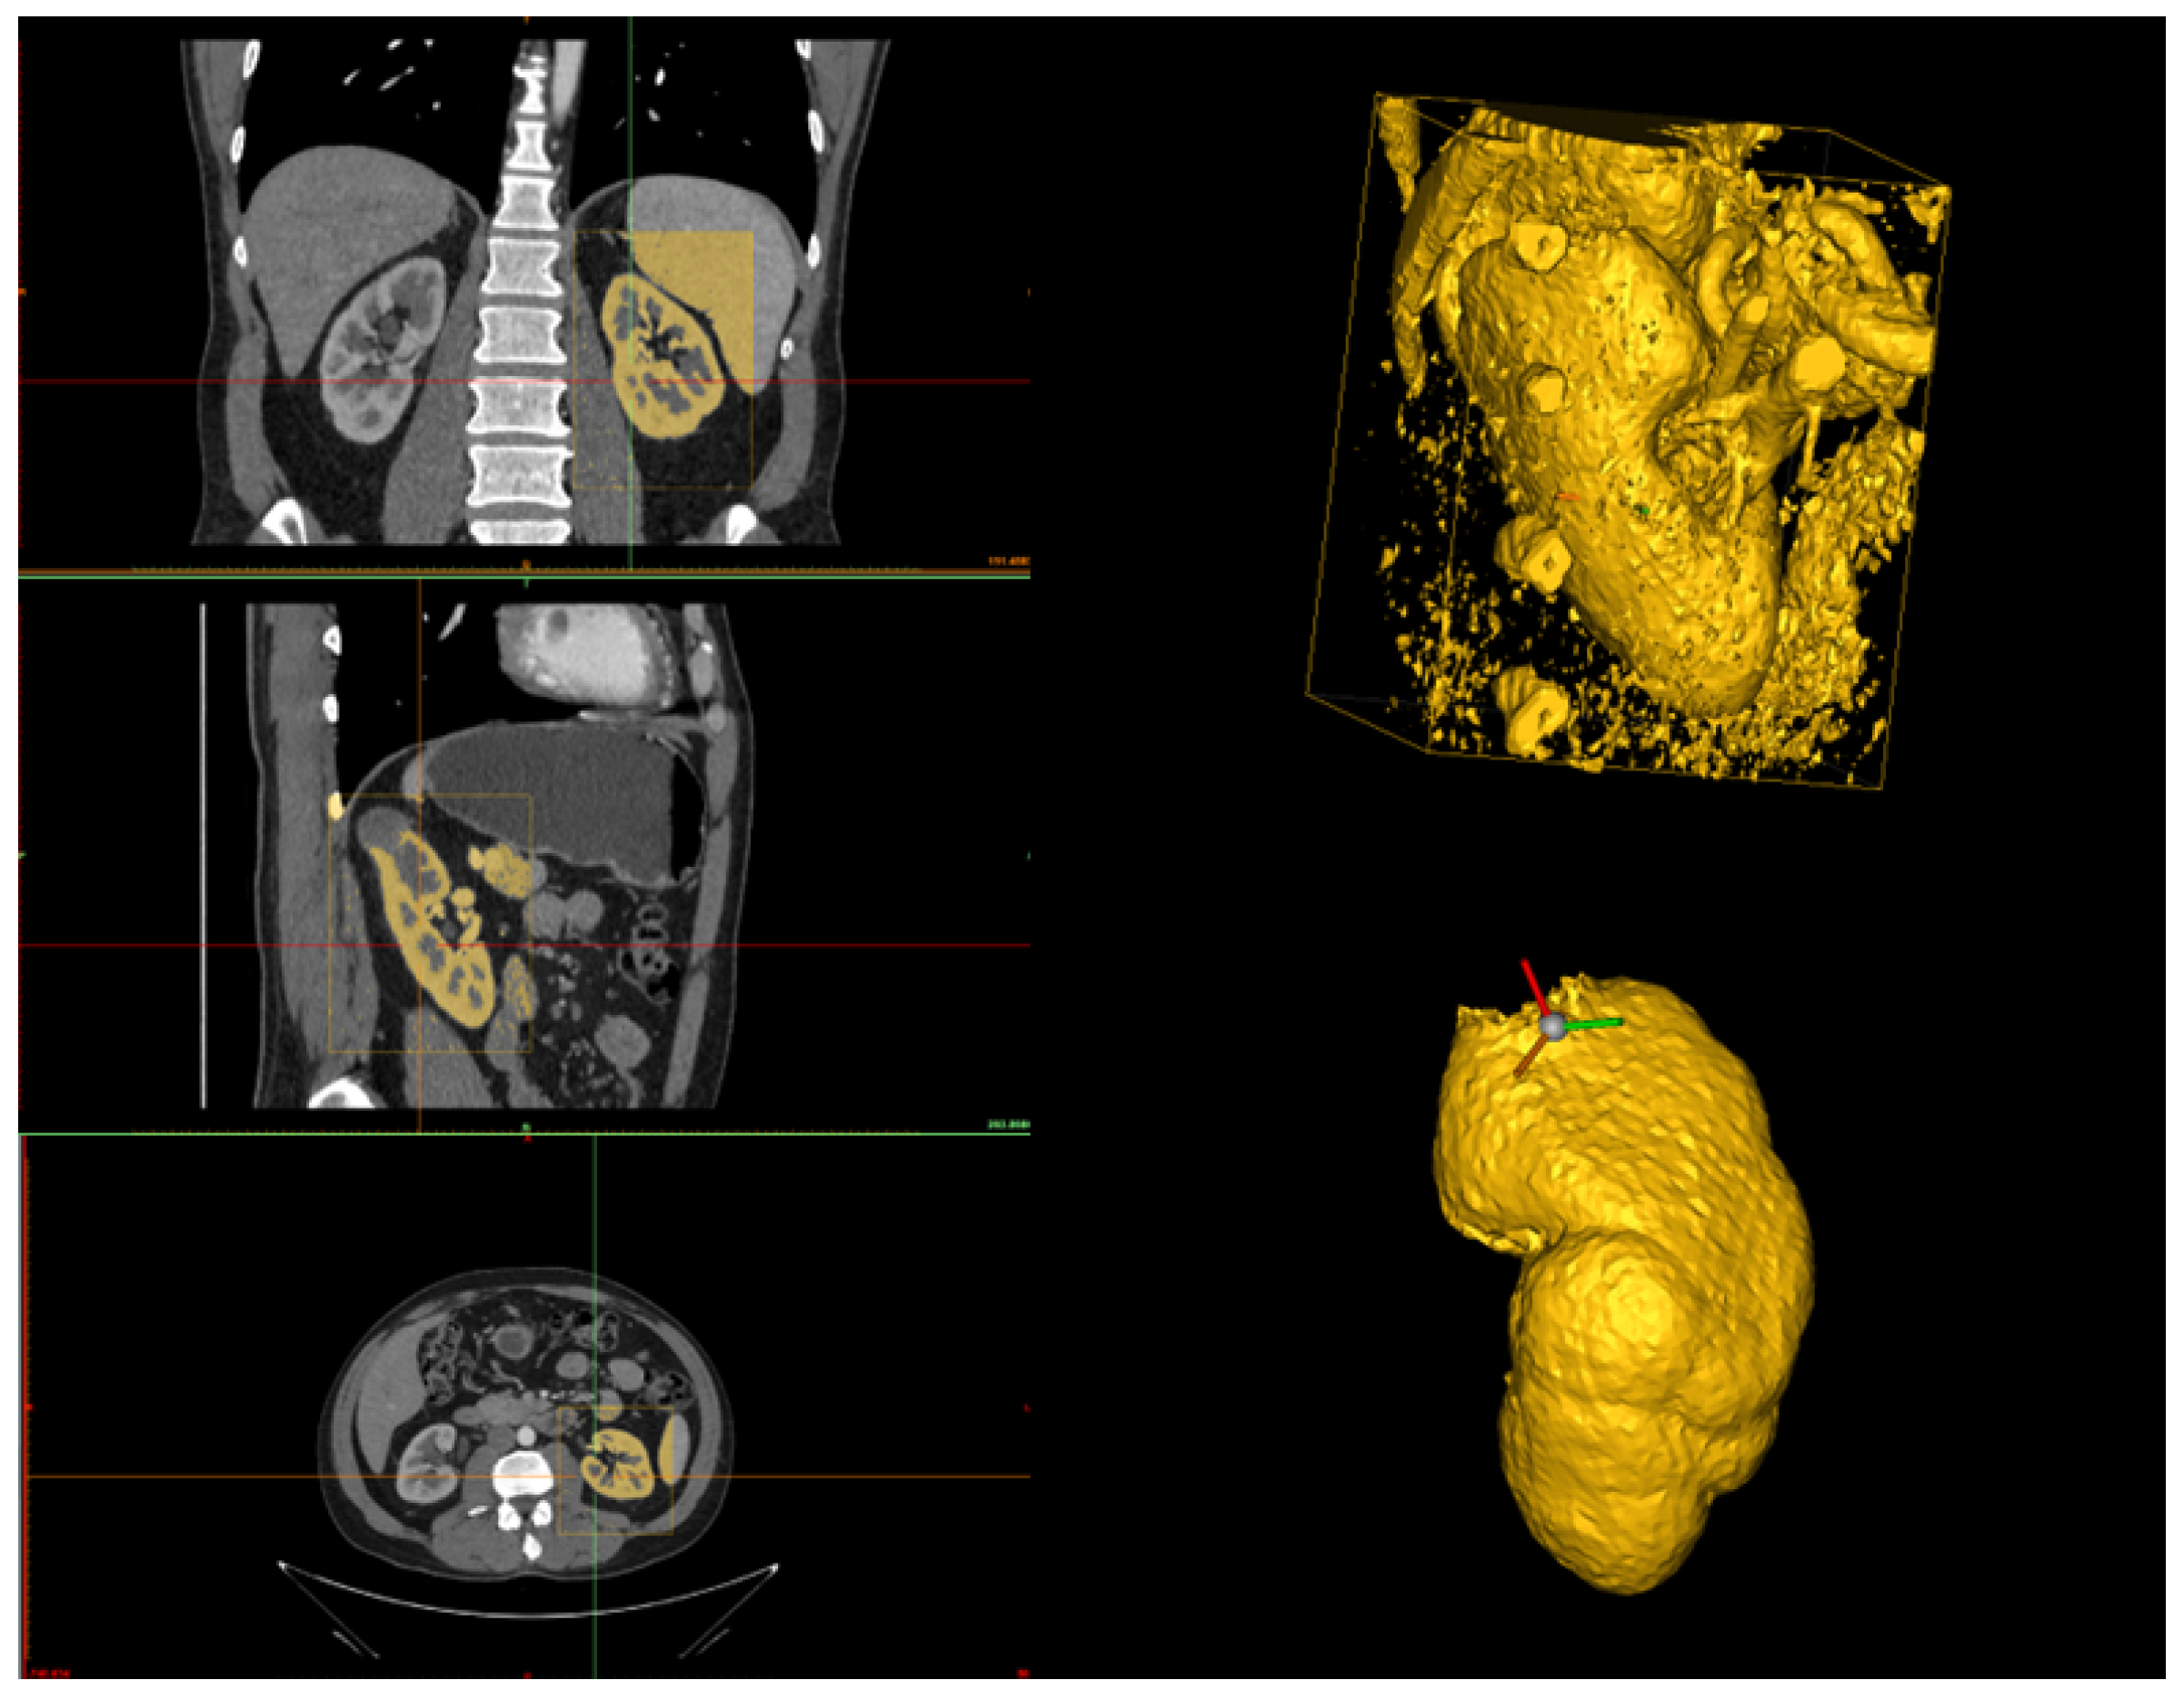

The human operator can set the HU range by choosing upper and lower bounds to highlight all the kidney structures and minimize cavities and holes in the kidney model (see Figure 2). Since the quality of the CT scan significantly influences the HU range, it is difficult to define a universal range. However, based on our experience with high-quality CT scans, the recommended range is (80–1969) HU. In the case of lower-quality scans, these limits can be adjusted to achieve an optimal reconstruction. Additionally, after setting these values, it is advisable to retain only large regions and automatically fill small holes. Once the segmentation of the region of interest (that is, a bounding box) is performed, the result is the 3D model of the kidney, together with other smaller parts from the surrounding tissues (see Figure 3).

Figure 3. On the left-hand side, the selection of the region of interest in the three planes (axial, coronal, and sagittal) is shown, where the region defined in yellow represents the kidney based on a threshold application. On the top right-hand side, the 3D reconstruction after the threshold application is displayed. On the bottom right-hand side, the 3D reconstruction after manual cleanup, where all surrounding structures have been removed, leaving only the kidney.